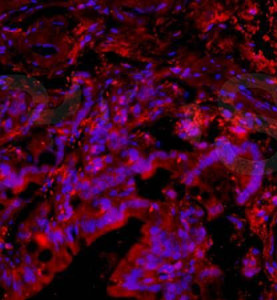

Anti-PACAP antibody GTX37576 from GeneTex | Biocompare.com。Anti-Desmin antibody [Y66] - Low endotoxin, Azide free。Anti-Desmin antibody [Y66] - Low endotoxin, Azide free。7820 INHEEL SLIPON | MUUM。。x1 red strawberryx1 pink strawberryx1 pink tigerx1 seal x1 pig

![Anti-Desmin antibody [Y66] - Low endotoxin, Azide free Anti-Desmin antibody [Y66] - Low endotoxin, Azide free](https://content.abcam.com/products/images/desmin-antibody-y66-low-endotoxin-azide-free-ab216616--immunohistochemistry-formalin-pfa-fixed-paraffin-embedded-sections-img128436.jpg)

![Anti-Desmin antibody [Y66] - Low endotoxin, Azide free Anti-Desmin antibody [Y66] - Low endotoxin, Azide free](https://content.abcam.com/products/images/desmin-antibody-y66-low-endotoxin-azide-free-ab216616--immunohistochemistry-formalin-pfa-fixed-paraffin-embedded-sections-img135003.jpg)